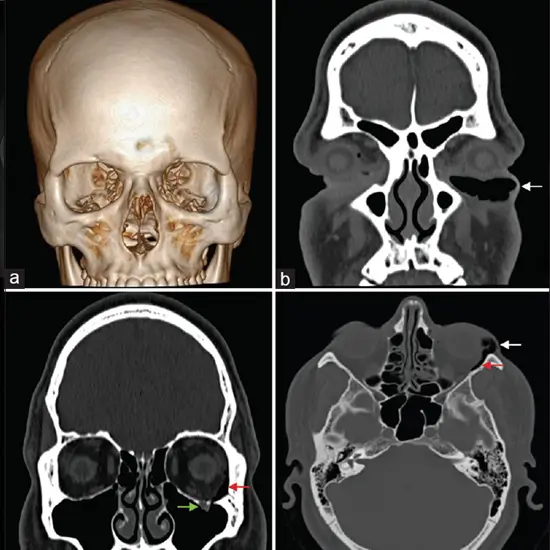

NCCT Face is a plain study of the face. It is a non-invasive imaging procedure to diagnose fractures and diseases affecting your jaw or facial bones.

• To detect the fractures of the facial or jaw bones.

• To assess diseases affecting the air-filled cavities of bones around the nose called sinuses.